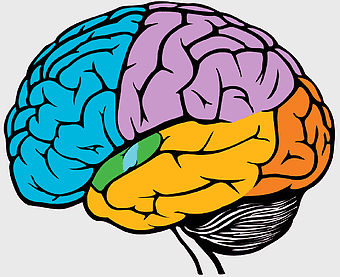

human brain illustration, cerebrum structure, cartoon brain image, pink brain graphic, brain anatomy diagram, neural system visualization, cognitive function art -

human brain illustration, brain anatomy diagram, neurologist reference image, homo sapiens brain structure, cerebral cortex depiction, neural network visualization, brain lobes outline -

human brain drawing, color brain illustration, brain anatomy art, neurology artwork, cerebral cortex diagram, brain lobes visualization, neural structure graphic -

pink brain illustration, cerebrum cartoon design, human brain structure, creative brain icon, brain anatomy diagram, cognitive function art, neural network graphic -